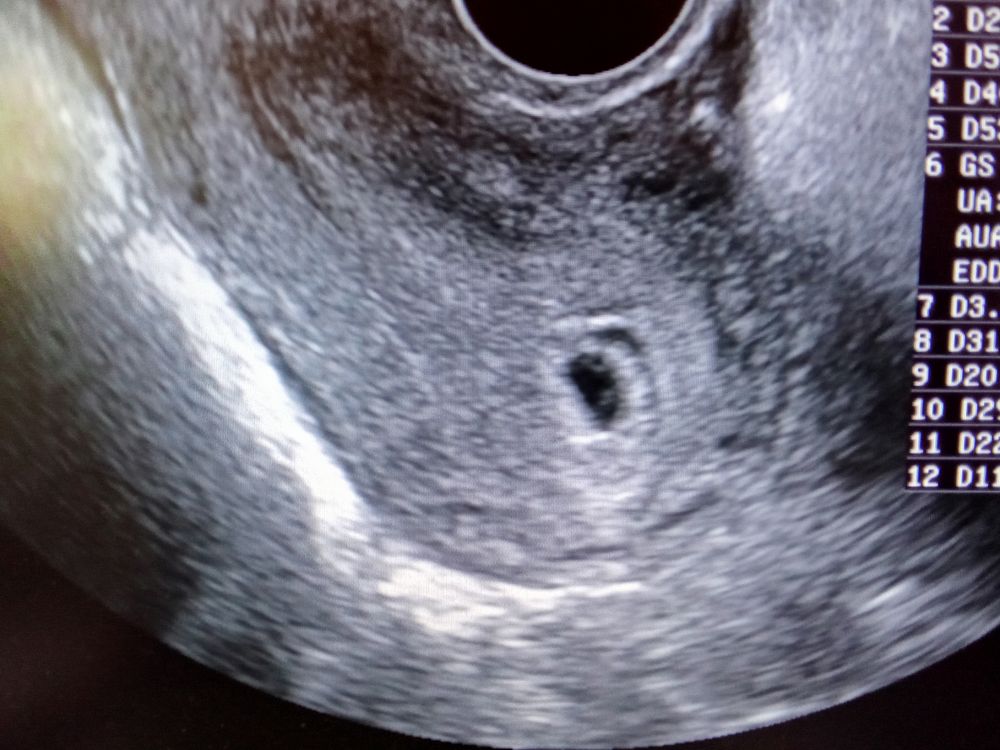

Мне кажется или на УЗИ двойня? Беременность 5 недель и 5дней, сердцебиение пока что не слышно. Хгч ещё не сделала . Узист про это ничего не говорил, сказали только про гематому

навряд ли двойня) Там скорее всего желточный мешочек и эмбриончик

А похоже) ЖМ и эмбрион не могут быть в разных углах ПЯ) Потом напишите что в итоге!

Вопрос не по теме, а какой у вас размер пя? Насчет вашего вопроса - точно вижу один жм, а вот что второе , непонятно)) тоже интересно, что у вас будет в итоге!

Эмбриончик и желточный мешок

Гематома есть точно,её видно